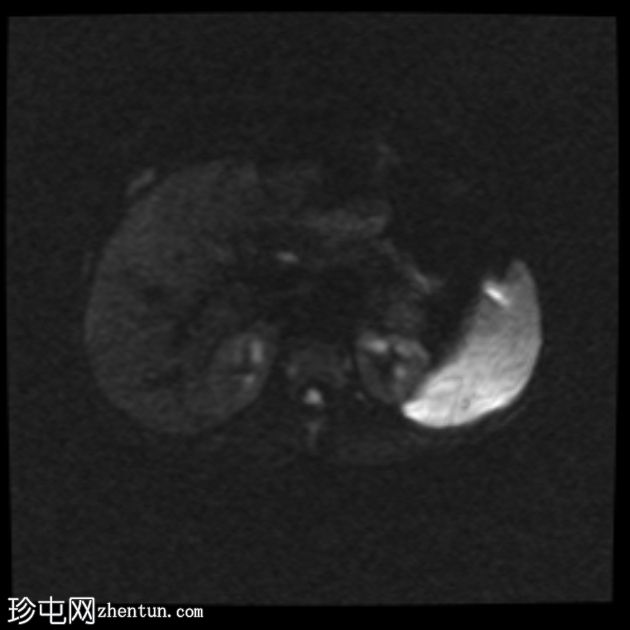

轴位

DWI序列

子宫前倾位,分区解剖结构正常。矢状位序列可见子宫前壁肌层局灶性边界不清的低信号病灶,但在后续序列中未见明显,符合短暂的生理性子宫肌层收缩表现。

双侧卵巢大小及卵泡活动均正常。未见囊性或实性肿块。

该病例的盆腔器官MRI表现与患者年龄(14岁)相符,子宫位置正常,分区解剖结构正常,双侧卵巢大小及卵泡活动均正常,未见囊性或实性肿块。

此外,MRI还意外发现子宫肌层局灶性病变,T2信号低,易被误诊为子宫肌瘤。然而,该病变在后续序列中消失,符合短暂的生理性子宫肌层收缩所致。